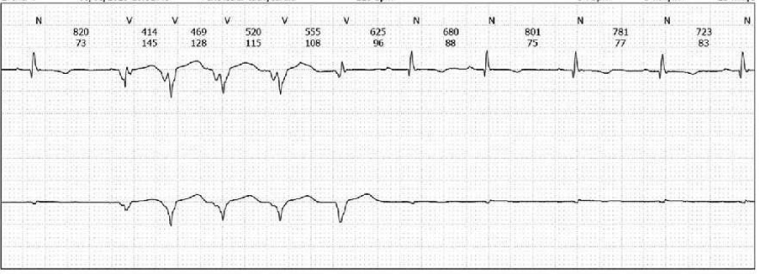

In the emergency department, a physical examination was undertaken, which was unremarkable, and given the episode of syncope, an ECG was performed (figure 2):

Figure 2: Baseline ECG demonstrating sinus rhythm (HR 93bpm), normal axis (+34o), PR interval 146ms, intraventricular conduction delay (QRS duration 86ms), delayed R wave progression, repolarisation abnormalities (T wave inversion laterally, flat inferiorly), and a normal QT duration (QTc 438ms).